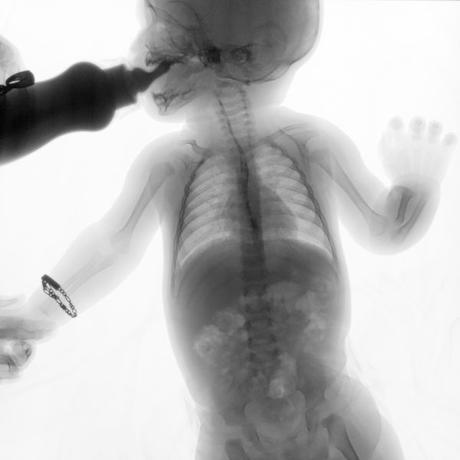

ESTUDIO SOLICITADO: SERIE ESOFAGOGASTRODUODENAL.

Se realiza Esofagograma con material de contraste baritado, por vía oral y por medio de control fluoroscópico se toman distintas proyecciones observando lo siguiente.

Se observa mecánica de la deglución con adecuado paso de medio de contraste de faringe a esófago sin presencia de defectos de llenado depósitos anómalos o fuga del mismo.

ESÓFAGO se observa de situación, calibre y trayecto normal. Contornos regulares y bien definidos. No se observan depósitos anómalos, defectos de llenado o fuga del medio de contraste.

UNION ESOFAGOGASTRICA se observa con calibre y situación normal. Sin observar reflujo a las maniobras de valsalva

ESTOMAGO se observa en su situación habitual, distendido, sin defectos de llenado.

- Actualmente no se demuestra Reflujo gastro-esofágico.

- Estudio de apariencia normal.